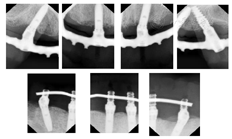

②上颌牙槽嵴黏膜翻瓣,清创炎性软硬组织,平整牙槽嵴顶骨嵴,在自由手操作下分别于12、15、22、25区植入4枚Nobel种植体,旋入复合基台,其中12、15、22区选择植入Nobel Speedy4.0x13mm种植体,25区选择Nobel Active4.3X11.5mm种植体,四颗种植体均利用鼻底皮质骨加强固位,初期稳定性均达到35N.cm(图5)。

③同上颌方法,平整牙槽嵴后于右下颌42、45区分别植入Nobel Speedy4x13mm种植体,均获得35N.cm的初期稳定性,左下颌区牙槽骨骨缺损明显(图6A),延期种植。45区为倾斜植入,放置30度复合基台,42放置球基台(图6B)。下颌种植术后拔除了原预留用作可摘义齿基牙的38、48。下颌过渡义齿利用植入的2枚种植体辅助支持固位,制作种植覆盖义齿过渡修复体(图7)。

术后1个月(2017年3月22日)复诊上下颌术区牙龈黏膜愈合良好,下颌复合基台及球基台周围可见软垢滞留,进行口腔卫生健康教育指导(图8A)。术后3个月(2017年5月17日)复诊X线检查示上下颌种植体骨结合良好(图8B、C)